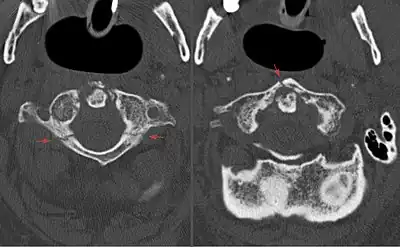

A Jefferson fracture is a bone fracture of the anterior and posterior arches of the C1 vertebra,[1] though it may also appear as a three- or two-part fracture. The fracture may result from an axial load on the back of the head or hyperextension of the neck (e.g. caused by diving), causing a posterior break, and may be accompanied by a break in other parts of the cervical spine.[1]